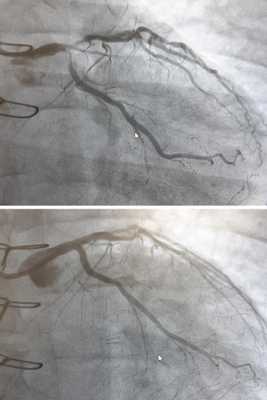

- коронарография (рентгенологическое исследование сосудов с помощью контрастного вещества, часто сочетается с хирургическим методом лечения ИБС - стентированием),

![Коронарография до и после стентирования]()

Коронарная ангиопластика и стентирование

Это современная технология восстановления проходимости коронарных артерий при ИБС. Смысл заключается в раздувании атеросклеротической бляшки специальным баллоном и укреплении сосудистой стенки металлическим каркасом - стентом. Коронарная ангиопластика проводится без разрезов у пациентов с тяжёлой стенокардией или инфарктом миокарда.